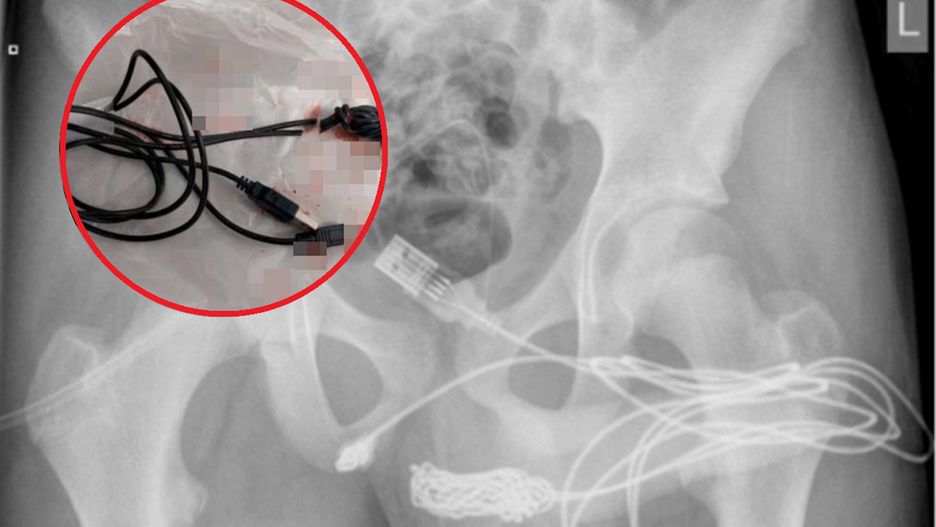

Chłopiec nie chciał się przyznać lekarzom, że za pomocą kabla USB, próbował zmierzyć długość penisa. Zrobił to dopiero, gdy jego matka wyszła z gabinetu. Medycy bezskutecznie próbowali wyjąć kabel. Po wykonaniu prześwietlenia okazało się, że jest to poważny przypadek.

Lekarze wykonali prześwietlenie

Lekarze wykonali prześwietlenie © Facebook